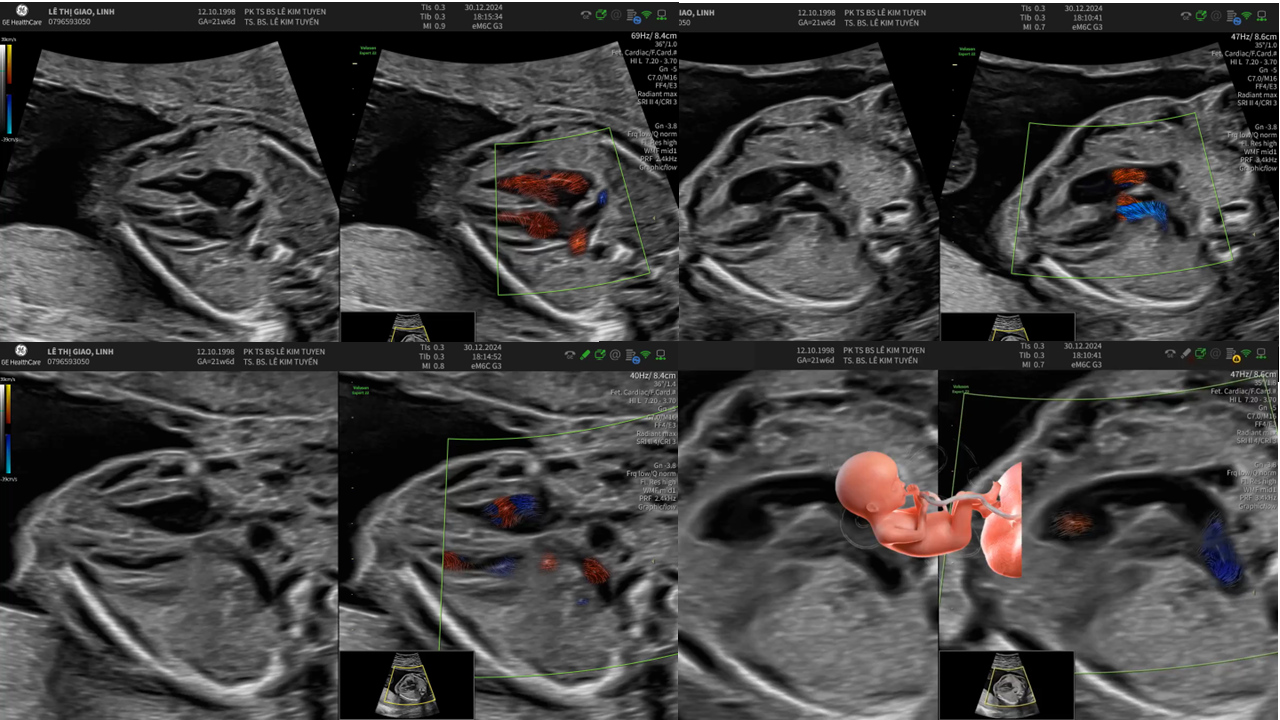

Áp dụng công nghệ Graphicflow trong phát hiện bệnh tim bẩm sinh cần cấp cứu sơ sinh

TS. BS. Lê Kim Tuyến

Bệnh viện Tim Tâm Đức